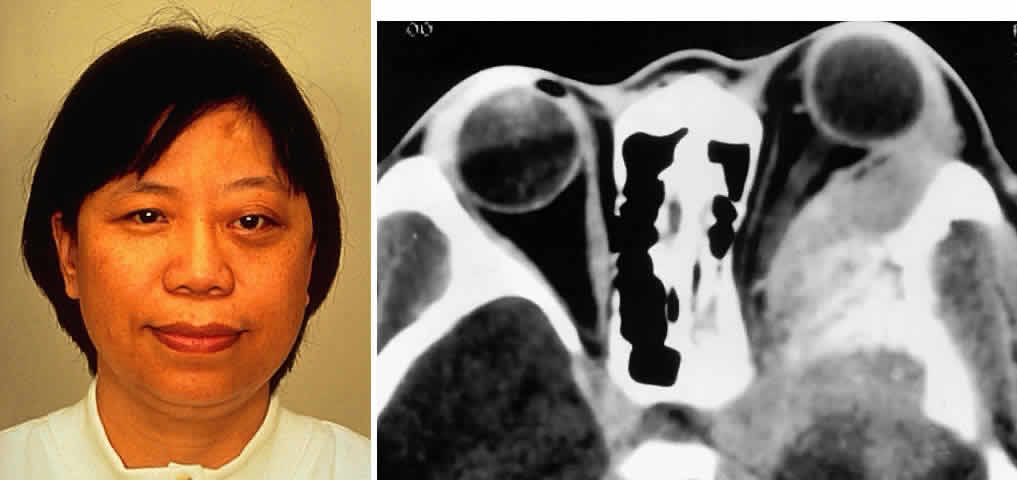

Meningiomas of the sphenoid wing are prone to extend into the orbit along the lateral wall as an en plaque component (Fig. 4). These desmoplastic, infiltrative lesions generally have some element of hyperostosis. The orbital and visual manifestations reflect the location of the mass, with the more medial tumors causing cranial nerve palsies, visual deficits, and venous obstructive signs and symptoms (e.g., edema, chemosis). More remote tumors are manifested by raised intracranial pressure or mass effect. Tumors of the greater wing of the sphenoid are evidenced by fullness of the temporalis fossa and proptosis, with intracranial symptoms occurring as a late symptom (Fig. 5). Olfactory groove meningiomas present with lost sense of smell, personality changes, papilledema, or apical orbital infiltration or compression.

Fig. 4. A 36-year-old white woman presented with a 3-month history of progressive left proptosis associated with a retrobulbar pressure sensation. On external examination, she had bossing of the temporalis fossa and a proptosis of 9 mm axially, with a slight downward displacement of the globe. Ocular ductions were full, and there was no evidence of optic nerve compromise. CT scan on axial (A) and coronal (B) views confirmed a hyperostosing sphenoid wing meningioma with soft tissue components in the posterolateral orbit and anterior middle cranial fossa. During the next 20 months, her proptosis progressed to 11 mm, accompanied by increasing headaches and ocular pain, ocular restriction, and blurred vision in abduction. She underwent tumor resection with a combined frontotemporal orbitozygomatic approach, and she remains without evidence of recurrence 5 years after surgery. Visual function was preserved, and proptosis decreased to 2 mm.

Fig. 5. A 48-year-old Chinese woman had undergone previous frontotemporal craniotomy and partial excision of a left sphenoid wing meningioma. She presented 6 years later with progressive proptosis, visual loss, and numbness of the left cheek and upper teeth that developed during the preceding 2 years. On external examination, she had fullness of the temporalis fossa, an axial proptosis of 11 mm, and downward displacement of the left globe 2 mm (A). Ocular ductions were moderately restricted in all fields of gaze. She had no light perception, marked optic disc pallor, and an optociliary shunt vessel. CT scan revealed an extensive regrowth of meningioma involving the sphenoid wing, with soft tissue components in the temporalis and middle cranial fossae, parasellar region, and orbit, shown here on axial view (B). The lesion also involved the cavernous sinus and pterygopalatine fossa. She underwent a combined resection via the frontotemporal orbitozygomatic approach, followed by radiotherapy (50 Gy in 25 fractions over 5 weeks) for residual components in the cavernous and sphenoid sinuses. Two years after surgery, she remains comfortable and without radiographic evidence of tumor regrowth. Proptosis was reduced to 1 mm axially.